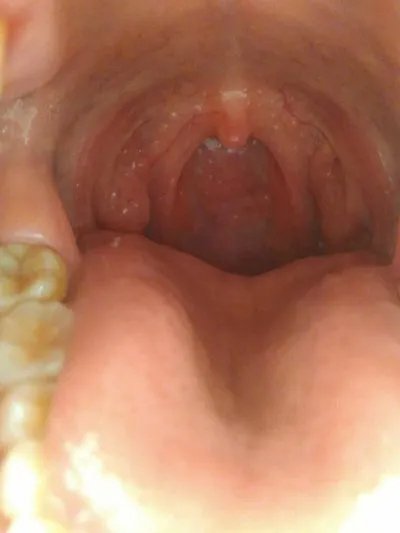

咽喉炎症状?

,咽喉炎症状? 急性咽炎时,除一些咽痛外,还可出现发热、头痛、食欲差,大便干、口渴等。如果治疗不及时,会反复发作,可转为慢性,若感染可导致急性鼻炎、急性中耳炎,向下发展,可侵犯喉、气管等下呼吸道,引起急性喉炎、气管炎、及肺炎,若毒素侵入血液循环会发生全身表现。

咽喉部的炎症会造成咳嗽、喘息困难等,也会出现呼吸道疾病很多。咽喉部肿胀会影响食物的吞咽,还会感到非常疼痛。咽喉炎是临床上的常见病和多发病,有急、慢性之分,属于上呼吸道感染的一部分。